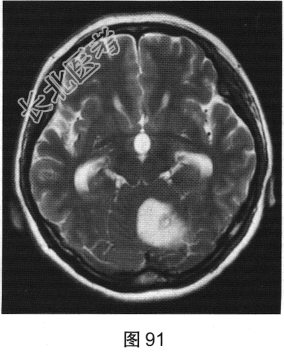

- [材料题] 患者女性,51岁,因“头晕、恶心进行性加重1个月余,伴呕吐5小时”就诊。患者于1个月前出现头晕症状,伴恶心,无视物旋转、头痛、走路不稳,无言语改变、意识障碍。患者症状反复发作并进行性加重,2周前间断出现走路不稳,似醉酒样步态,倒向左侧;5小时前出现头晕、恶心,并呕吐胃内容物,站立不稳。既往有高血压病史3年,血压控制尚可。查体:轮椅推入病房,可见步态不稳,神志清楚,应答正确,无吟诗样及爆炸样言语,遵嘱活动,双侧瞳孔等大正圆,对光反射灵敏,四肢活动可,肌力、肌张力未及异常,指鼻试验、双侧轮替试验阴性,双侧跟膝胫试验欠稳准,双侧膝反射及跟腱反射正常,双侧病理征未引出,闭目难立征不能配合。实验室检查:外周血白细胞计数15.29×109/L,中性粒细胞百分比92.1%,二氧化碳18.8mmol/L,血糖7.05mmol/L;心肌酶、凝血试验正常。

- 多项选择题2.[提示]患者行CT及MRI检查,如图90~图95所示。CT及MRI上的阳性影像学表现包括( )

A、MRI示右侧囊实性病变

C、MRI示左侧囊实性病变

D、MRI示右侧少许水肿

H、MRI示左侧少许水肿